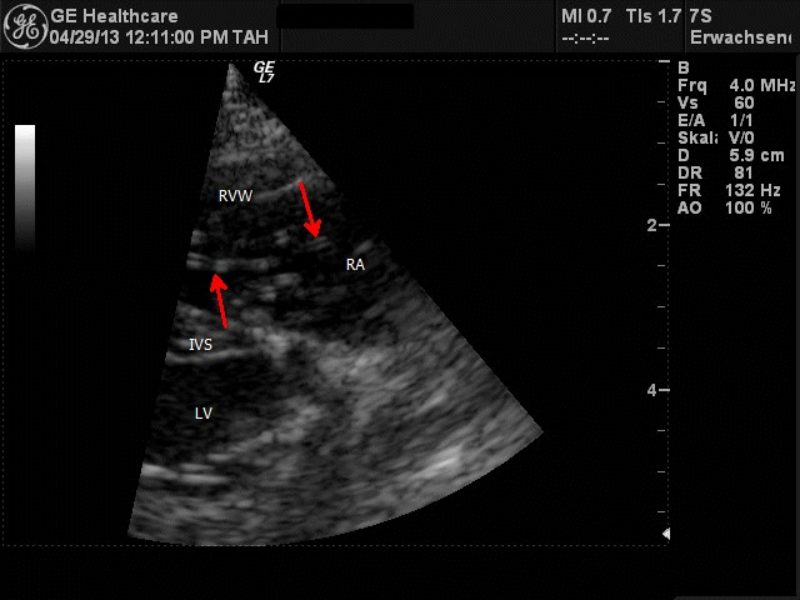

In der Sprechstunde zeigte sich Quax nun in stabilem Zustand. Beim Abhören des Brustraumes fielen ein Herznebengeräusch rechts mit einer Intensität 3/6 (Intensität wird in 6 Grade eingeteilt / Grad 3: moderate Lautstärke) und abnorme Atemnebengeräusch auf. Der Puls war kräftig und der Hund zeigte keine erneute Synkope während der Untersuchung. Wir fertigten Röntgenbilder des Brustraumes an, die eine leichte Herzvergrößerung mit Betonung des Rechtsherzens und wolkig-fleckige Verschattungen der Lunge im Hilusbereich und von da aus in den kaudalen Lungenlappen ziehend zeigten. In der Echokardiographie (Ultraschalluntersuchung des Herzens) ergab sich dann ein ungewöhnlicher Befund: die rechte Herzkammer war deutlich erweitert, und in ihr schwappte ein regelrechtes großes Knäul aus echogenen Doppellinienstrukturen im Blutfluss des Herzens hin und her. Die Pulmonalarterie, die aus der rechten Herzkammer in die Lunge führt, war erweitert, und auch da waren charakteristische Doppellinien zu sehen. Selbst im rechten Vorhof und bis in die davor liegende Vena Cava konnten sonographisch Doppellinien verfolgt werden. Dies war das typische Bild eines sogenannten Cavasyndroms, ausgelöst durch adulte Herzwürmer, die sich im Herzen aufhalten. Ein zusätzlich durchgeführter Herzwurm-Antigen-Test verlief dieses Mal positiv.